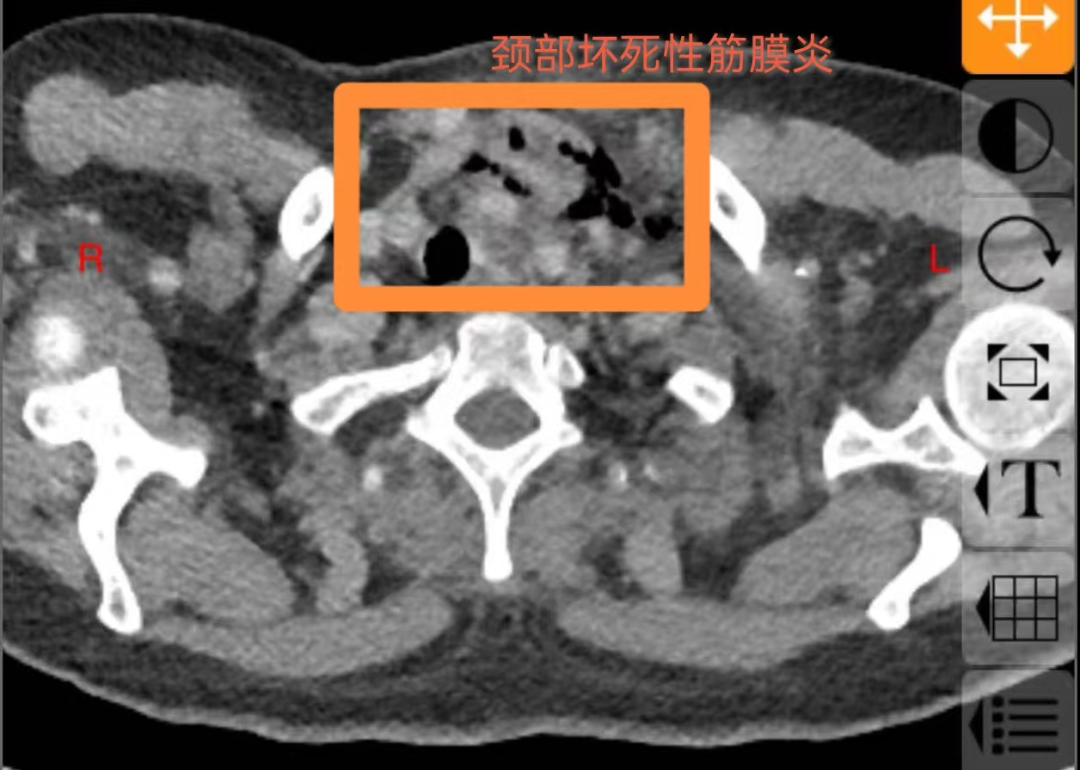

60岁的庄女士未曾想到,一场看似寻常的牙痛,竟会迅速发展为危及生命的重症。庄女士糖尿病多年未经规范治疗,口腔卫生欠佳,口内牙齿时不时疼痛、松动、脱落,患者总认为牙疼是小毛病,吃点甲硝唑就好了,从未重视。5 天前,左下后牙疼痛后患者依旧未经重视,很快就出现咽部、颈部疼痛伴吞咽困难,在当地医院接受抗感染治疗,病情却未见好转,还出现难以忍受的胸部疼痛,叠加吞咽、呼吸困难等症状,被救护车紧急送往西安市红会医院耳鼻咽喉头颈整形修复科。经诊断,庄女士为 “颞下、咽旁、翼下颌、颌下间隙感染,颈部坏死性筋膜炎、下行性坏死性纵膈炎”,病情及其危重,需要头颈外科、胸外科、内分泌科等多学科联合救治,此类疾病非常凶险,死亡率较高,为患者办理住院后转入急诊重症监护室(EICU),一场与死神的赛跑就此拉开序幕。

颈部坏死性筋膜炎

耳鼻咽喉头颈整形修复科龚龙岗主任、马戈副主任团队第一时间全面评估病情,发现庄女士不仅存在口腔颌面多间隙感染,还并发左侧颈部坏死性筋膜炎、下行性坏死性纵膈炎、右侧包裹性脓胸,叠加2型糖尿病(血糖控制不佳)、高血压病1级(极高危)、电解质紊乱等基础疾病与并发症,病情复杂凶险。面对这一局面,科室迅速启动多学科联合救治机制,一场跨科室的协同作战即刻展开 —— 胸部外科、EICU、内分泌代谢科、神经内科、营养膳食科等科室专家迅速集结,从各自专业维度切入,共同为庄女士制定个性化救治方案。